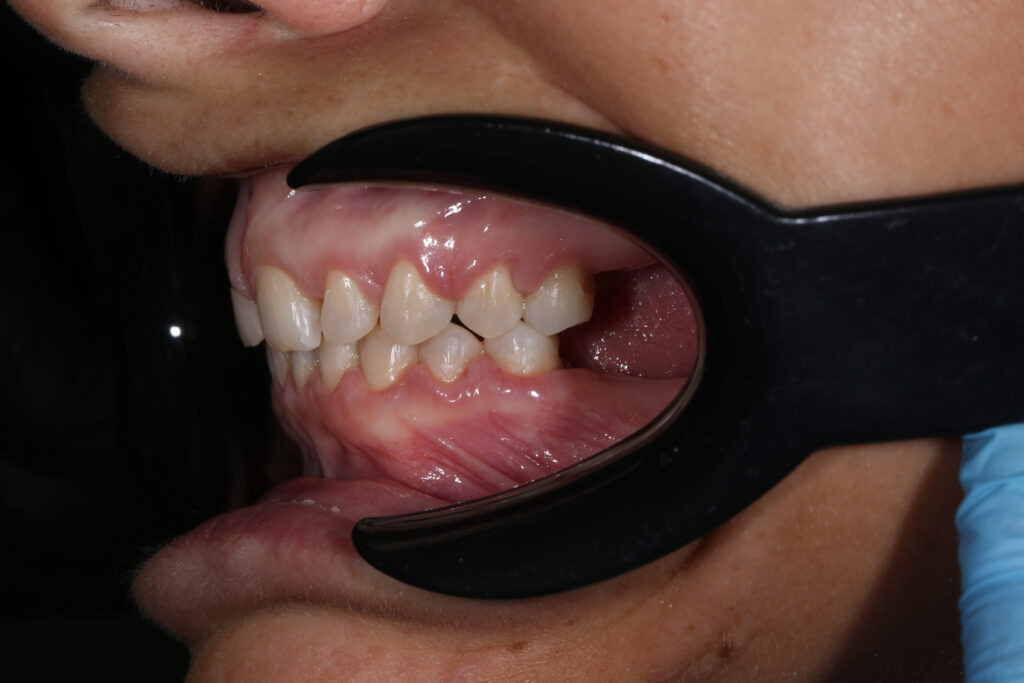

Ситуация до лечения

Из-за множественных давних удалений жевательных зубов, произошла деформация зубных рядов, зубы разъехались в область удаленных, что затрудняло протезирование в момент обращения к ортопеду.

Так же можно отметить сильное снижение высоты прикуса (верхние зубы на 100% перекрывали нижние, что вызывало хроническую травму десны), а также повышенную стираемость твердых тканей зубов, что является следствием повышенной нагрузки, которую много лет испытывали передние зубы, в связи с отсутствием жевательных зубов.